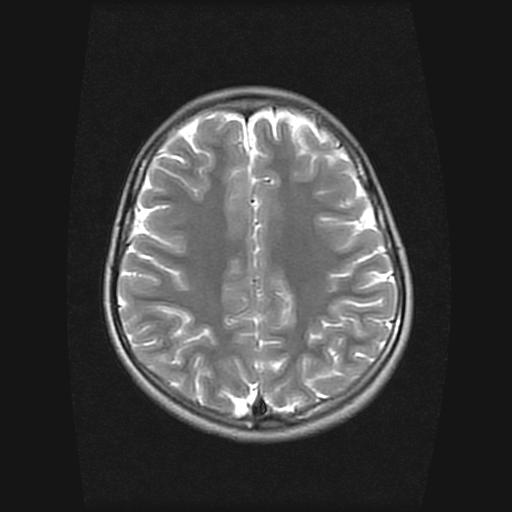

9岁女孩,三岁时诊断为癫痫,一直服丙戊酸钠,现患者一般情况良好,家长复查核磁片,看能否停药..

巨脑回

未见异常信号灶.

未发现异常信号。

停药要结合临床,如无发作可以停。